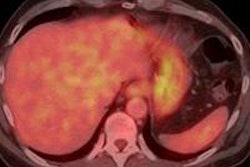

In PET imaging, more precise timing information on the coincidently detected gamma photons allows for improved suppression of background noise in the reconstructed image and better localization of the original decay event along the line of response between the two detectors. In current, top-of-the-line PET scanners, detectors have a working time resolution of around 400-600 ps, allowing tumors to be localized to within a 6-9 cm range along the line of response. In contrast, a machine with a time resolution of 200 ps would be able to reduce the range to just 3 cm.

Both tests reported similar and improved timings with the two detectors, with the best coincidence time resolution seen for the 2 x 2 x 3 mm crystals of only 85 ps -- an experimental record. For longer, 2 x 2 x 20 mm crystals of the size employed in current-generation PET systems, the best coincidence time resolution measured was 140 ps.